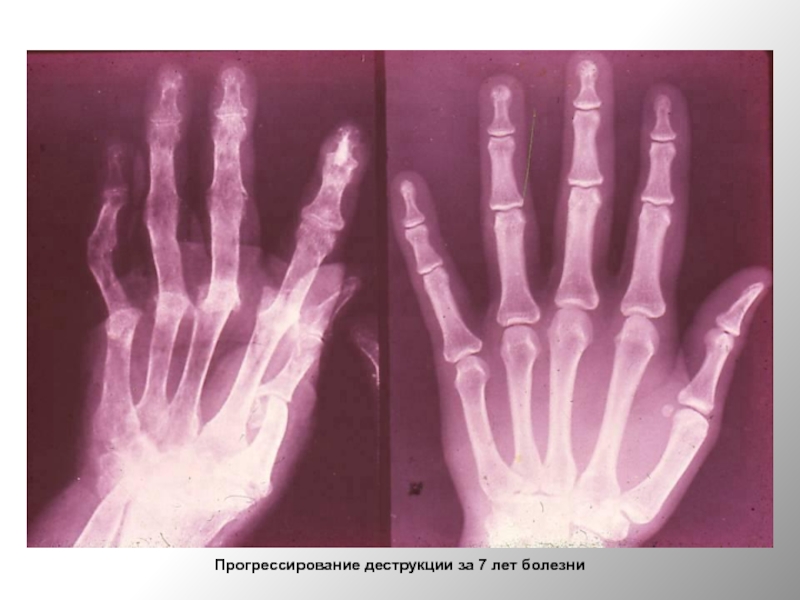

Слайд 50Прогрессирование деструкции за 7 лет болезни

Прогрессирование деструкции за 7 лет болезни